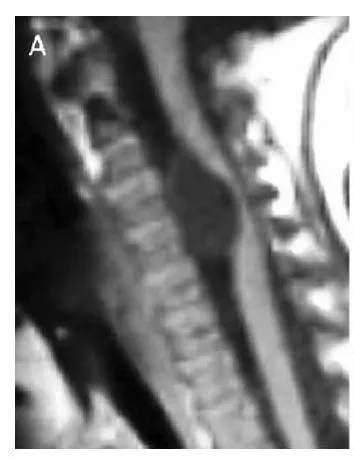

有个患者大概半年前开始觉得后背隐隐作痛,偶尔右手手指发麻,没当回事,以为是颈椎病或者睡觉压到了。后来麻木感越来越明显才去拍了个核磁,报告上写的是椎管内占位,考虑脊膜瘤。...

更新时间:2026-05-14 14:04:38